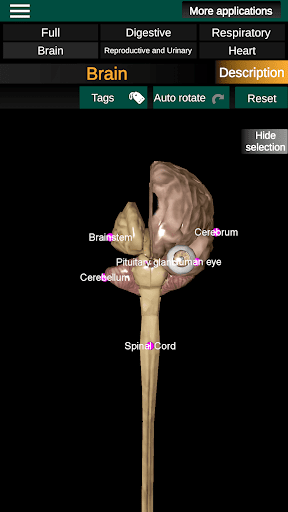

* Otak, yang meliputi otak, otak kecil, dan batang otak.